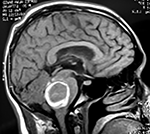

EJEMPLO DE CASO CLÍNICO (8)

Paciente femenino de 29 años de edad con historial de cefalea crónica que presenta súbitamente disdiadococinesia y dismetría izquierda.

El estudio de RMN presenta una lesión bien circunscrita en hemisferio cerebeloso izquierdo con periferia de predominio hiperintenso en T1 y T2, y centro hipointenso, edema perilesional mínimo, así como una imagen de un vaso venoso alimentador que recorre hacia el ángulo pontocerebeloso izquierdo.

Se realizó una craniectomía suboccipital paramedial derecha, así como un abordaje transcortical en el hemisferio cerebeloso izquierdo llegando a la región perilesional de aspecto amarillento, posteriormente se observa una lesión oscuro-verdoso de contenido hemático antiguo, retirando la cápsula y su contenido en la totalidad.

La evolución clínica de la paciente fue satisfactoria solo preservando la dismetría como secuela.

El resultado histopatológico fue consistente en angioma cavernoso.

El estudio de control de RMN se observa la brecha quirúrgica y ausencia de lesión (figs. 1, 2 y 3).

Figura 2:

Cortes axiales en ponderación T1, cambios postquirúrgicos.